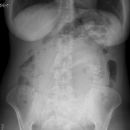

Abdomen

Ileus